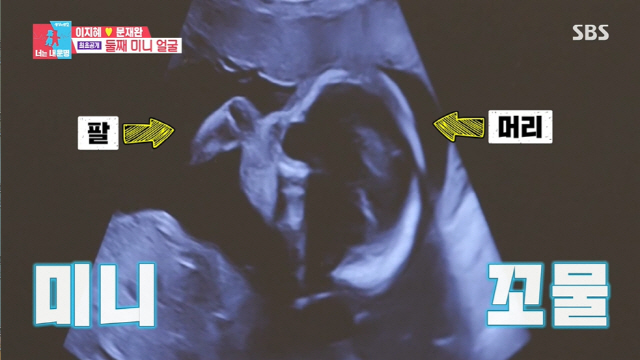

드디어 미니를 만나러 갈 시간, 태리에 이어 미니까지 돌봐 준 의사선생님을 만났다. 첫째 때보다 배도 더 많이 나왔지만 태교에도 신경을 못써 걱정하는 이지혜는 7주 차 콩알 미니를 봤던 것에 비해 확연히 보이는 미니를 만났다.

이지혜는 "난 하는 게 없는데 얘 스스로 잘 크는 것 같아"라고 감격해 했다. 선명하게 보이는 미니의 귀는 이지혜, 태리와도 닮아있었다. 미니와 손인사를 할 차례, 작지만 엄마를 향해 쫙 펼친 손에 이지혜는 미소 지었다.

가장 중요한 몸무게는 발육상태의 지표가 됐다. 머리둘레는 딱 표준, 배 둘레도 정확히 평균이어서 엄마 아빠를 안심하게 했다. 건강한 미니의 심장소리를 우렁차게 울려 이지혜를 감동받게 했다. 의사 선생님은 "얼굴이 잘 안 보이는데 달달한 거 먹으면 움직인다"라고 권했다. 의사선생님이 주신 쿠키를 먹는 이지혜 옆에서 문재완은 부스러기를 먹어 웃음을 자아냈다.

엄마 아빠를 보여주려고 돌아누운 미니의 모습에 이지혜는 "너무 신기해, 눈물 나"라면서 눈을 떼지 못하며 눈시울을 붉혔다. 문재완을 닮아 높은 코에 얼굴형도 닮아있는 미니는 태리와도 판박이였다. 이현이는 "저희는 첫째랑 둘째는 초음파부터 완전히 달랐다"라고 했다.